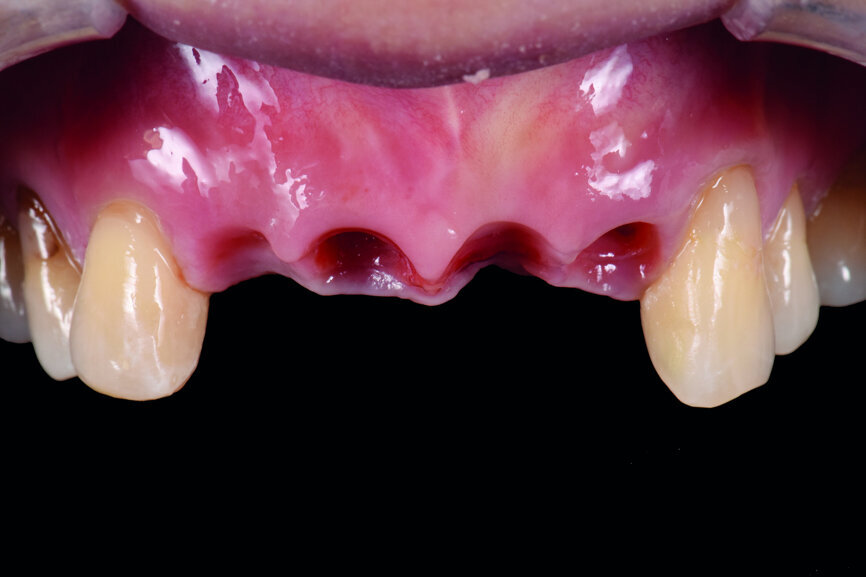

A 40-year-old female patient had sustained trauma to her anterior teeth caused by accidental syncope three weeks before. The clinical examination found that tooth #11 had been luxated; the crowns of teeth #12 and 21 had fractured, with the residual margin extending 3–5 mm below the gingiva and the teeth affected by Grade III mobility; and the crown of tooth #22 had fractured, with the residual margin at gingival level. There were no obvious abnormalities in the remaining teeth (Figs. 1–4). After excluding major systemic diseases, it was decided that she required fixed implant restoration with high demands regarding aesthetics and function.

Teeth #12, 21 and 22 were extracted. Tooth #11 underwent early implantation and tooth #22 immediate implantation with GBR (Figs. 5 & 6). After three months of healing, osseointegration had taken place. An implant level impression was taken for fabricating a provisional bridge supported by temporary abutments for teeth #12–22. The technician modified the shape of the artificial gingiva on the model in order to form the proper gingival curve and emergence profile, then finished the provisional bridge, while the dentist modified the gingival shape using an olive-shaped bur intraorally (Figs. 7–18).